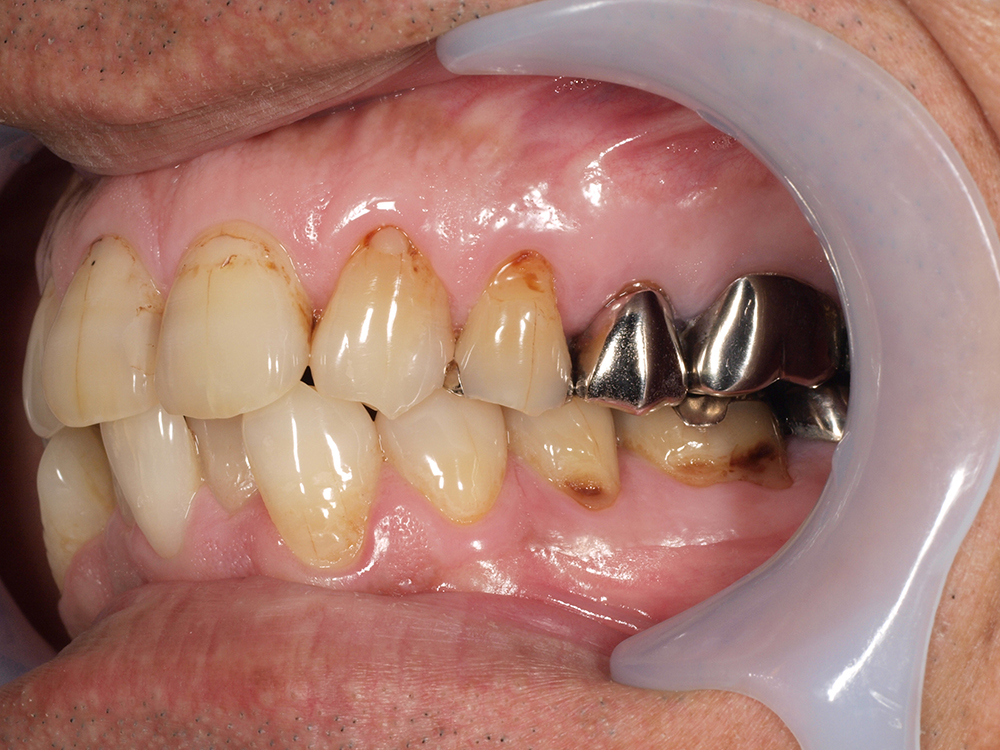

55歳 男性

- 主訴

- 前歯でしか咬めなく、食事を採るのに非常に困難で辛い

- 処置内容

- 上顎6本、下顎3本

- 治療費用

- 上顎:約230万(税込)下顎:約120万(税込)

- 治療期間

- 上顎:1年(仮歯まで8か月)下顎:8か月(仮歯まで5か月)

- リスク

- 上部構造物、仮歯の破折、術後の腫れ(3日)、人工歯根脱落リスクがあります